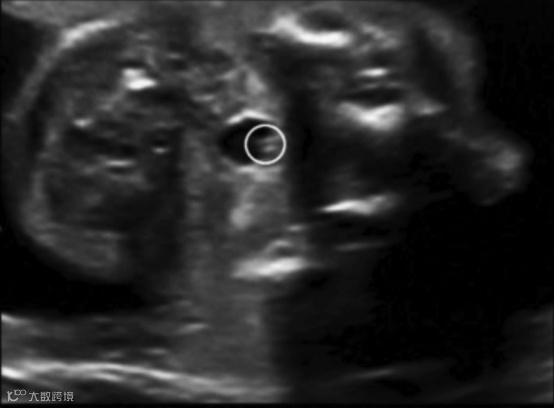

2.软腭线(如果软腭是好的,前面的硬腭也是好的)

完整的软腭线

3.软腭如果异常,再往前看硬腭线,由此确定单纯腭裂的程度。

完整的硬腭线

上述几个切面,最容易扫描的是硬腭线,常常作为筛查严重单纯腭裂的平面。

平时的筛查中,胎儿面朝探头时我们会常规扫查牙槽骨,此时略微倾斜探头即能找到硬腭线,继而软腭线,最后悬雍垂。